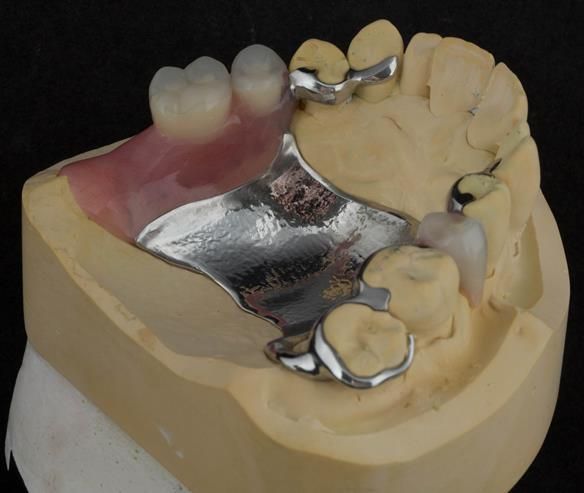

This newsletter describes in step by step detail Angela's transition through immediate partial dentures to crown supported definitive metal based dentures.

The clinical situation and treatment process is shown in detail below with photographs. I (Finlay Sutton) provided the clinical work and Rowan Garstang provided the technical work.